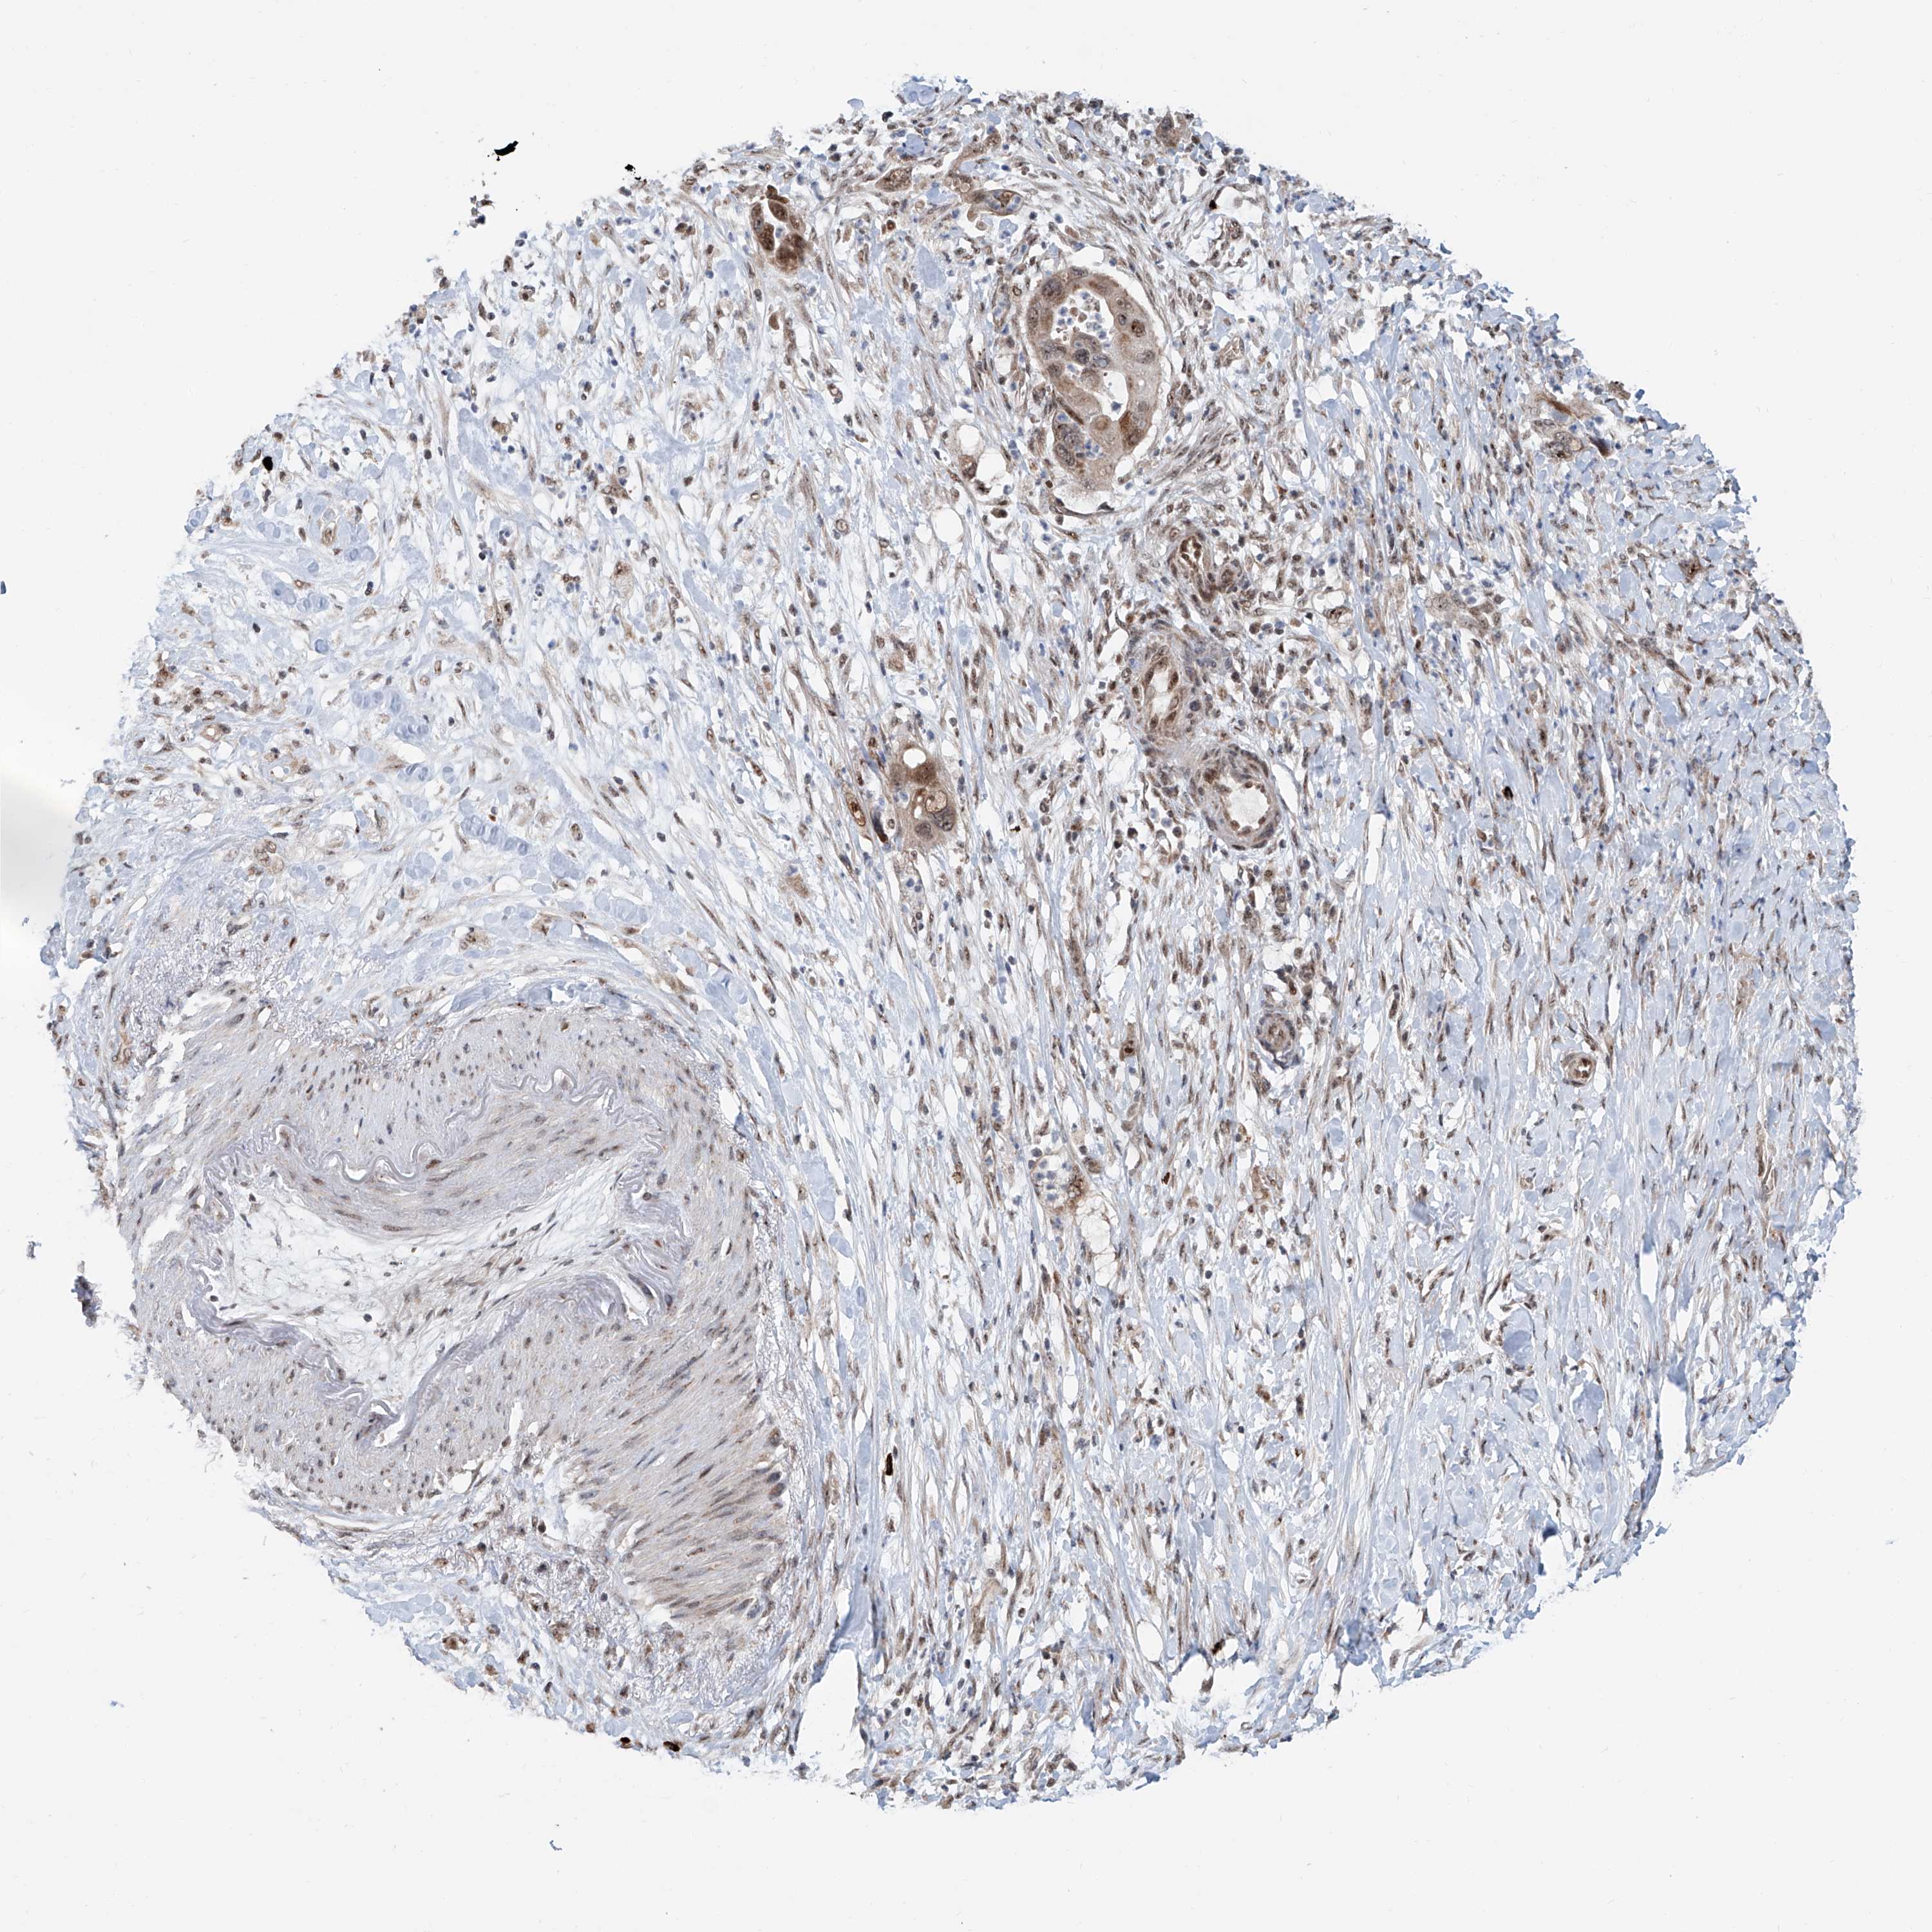

PANCREATIC CANCER - Protein expressioni

A mouse-over function shows sample information and annotation data. Click on an image to view it in a full screen mode. Samples can be filtered based on level of antibody staining by selecting one or several of the following categories: high, medium, low and not detected. The assay and annotation is described here.

Note that samples used for immunohistochemistry by the Human Protein Atlas do not correspond to samples in the TCGA dataset.

Antibody stainingi

Antibody staining in the annotated cell types in the current human tissue is reported as not detected, low, medium, or high, based on conventional immunohistochemistry profiling in selected tissues. This score is based on the combination of the staining intensity and fraction of stained cells.

Each image is clickable and will lead to virtual microscopy that enables deeper exploration of all samples and also displays staining intensity scores, fraction scores and subcellular localization as well as patient and tissue information for each sample.

Antibody HPA028467

Antibody HPA031255

Antibody HPA031256

Staining

High

Medium

Low

Not detected

Intensity

Strong

Moderate

Weak

Negative

Quantity

>75%

75%-25%

<25%

None

Location

Nuclear

Cytoplasmic/membranous

Cytoplasmic/membranous,nuclear

Adenocarcinoma, NOS